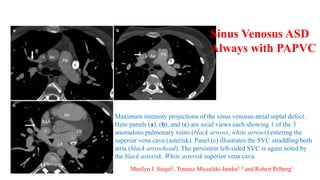

Maximum intensity projections of the sinus venosus atrial septal defect .

Here panels (a), (b), and (c) are axial views each showing 1 of the 3

anomalous pulmonary veins (black arrows, white arrows) entering the

superior vena cava (asterisk). Panel (c) illustrates the SVC straddling both

atria (black arrowhead). The persistent left-sided SVC is again noted by

the black asterisk. White asterisk superior vena cava.

Sinus Venosus ASD

Always with PAPVC

Marilyn J. Siegel2, Tomasz Miszalski-Jamka3, 4 and Robert Pelberg1